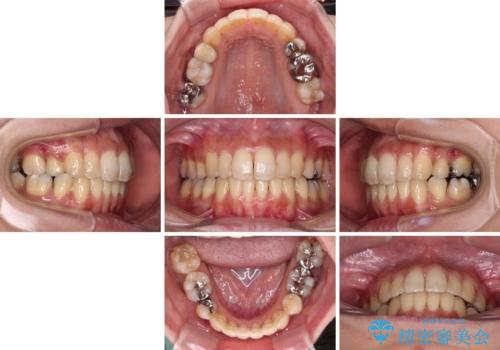

- 抜歯矯正の後戻りで前歯が突出してきていることを気にして来院された患者様です。

口元の突出感を改善するにあたり、抜歯矯正は行うことができないため、奥歯の後方移動とIPR(歯と歯の間を削る)により達成することとしました。

再度後戻りしたときに対応しやすいよう、インビザラインにて矯正治療を行うこととしました。

舌の突出癖がなかなか改善できず、IPRによる前歯の隙間が閉じきらずに、予定よりも長い治療期間となりました。